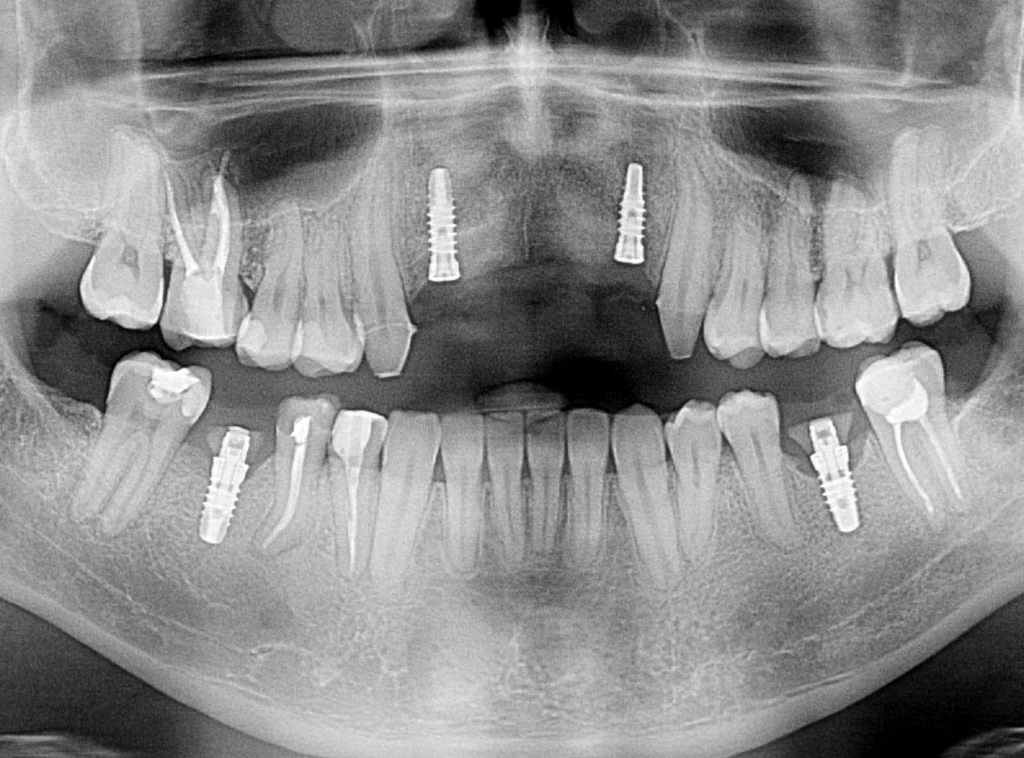

Szkolenie koncentruje się na przewidywalnych i bezpiecznych technikach augmentacji, w tym horyzontalnej i pionowej regeneracji kości, z dużym naciskiem na praktykę – uczestnicy wezmą udział w trzech warsztatach na preparatach zwierzęcych oraz zabiegach pokazowych (wideo), obserwując pracę doświadczonych wykładowców krok po kroku.

9:30 – 11:30 – Zabiegi na żywo lub VIDEO z zabiegów regeneracji kości.

15:15 – 16:45 – Warsztat. Wszczepienie implantu z jednoczasową regeneracją kości (samodzielne wykonanie zabiegu na preparacie zwierzęcym).

W swojej pracy nie uznaje kompromisów i stosowania półśrodków – stawia sobie za cel wybór najlepszych w danym przypadku metod kompleksowego leczenia. Podejmuje się nawet najtrudniejszych zabiegów regeneracji kości, podniesienia zatok szczękowych, implantologii stosowanej, pełnej odbudowy uzębienia i przywrócenia prawidłowych funkcji żucia. Wszystko po to, by zapewnić Pacjentom spektakularny efekt zdrowego i pięknego uśmiechu.